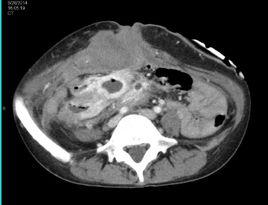

三、CT檢查:

腹壁硬纖維瘤CT表現具有以下特點:(1)腫塊起源於腹直肌和腹內斜肌,腫塊長軸與腹肌走形一致;(2)多為單發腫塊,腫瘤呈梭形或類圓形;(3)腫塊一般形態規則,但與肌肉分界欠清;(4)腫塊密度均勻,平掃時與肌肉密度相仿或稍低於肌肉,出血壞死鈣化少見。平掃腫塊密度與其內纖維母細胞、肌纖維母細胞與基質的比例有關。動態增強掃描動脈期病灶大部分呈不均勻輕度強化,門脈期持續強化,呈不均勻中重度強化,延遲掃描進一步強化。延遲強化趨於均勻,對診斷本病具有提示作用。